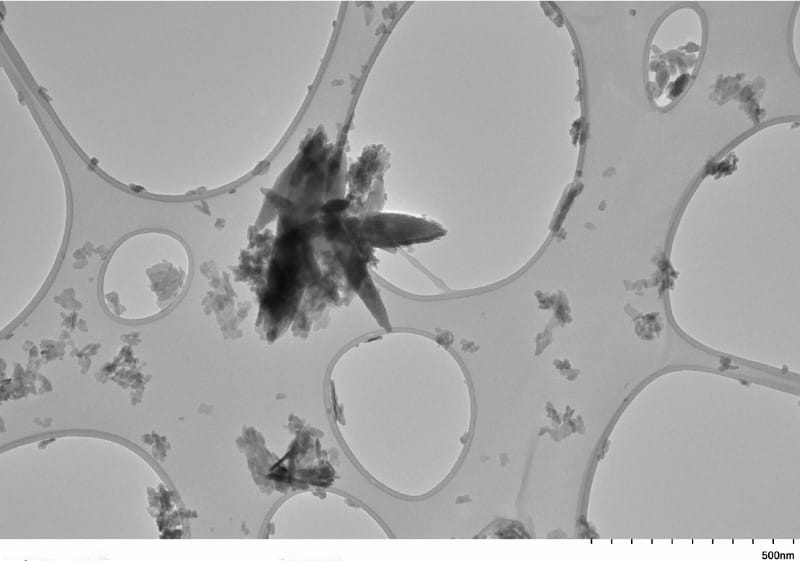

Microplastics and nanoplastics mainly result from larger plastic consumer products degrading in the ocean, soil, rivers, lakes or air. Microplastics are less than 5 millimeters in size – about the size of a pencil's eraser – while nanoplastics are microscopic at less than 1,000 nanometers. By comparison, a human hair is about 80,000 to 100,000 nanometers wide.